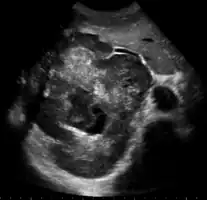

| Left lobe liver tumor in 50-year-old man | |

Upon discovery of a liver tumor, the main issue in the workup is to determine whether the tumor is benign or malignant. Many imaging modalities are used to aid in the diagnosis of malignant liver tumors. For the most common of these, hepatocellular carcinoma (HCC), these include sonography (ultrasound), computed tomography (CT) and magnetic resonance imaging (MRI). When imaging the liver with ultrasound, a mass greater than 2 cm has more than 95% chance of being HCC. The majority of cholangiocarcimas occur in the hilar region of the liver, and often present as bile duct obstruction. If the cause of obstruction is suspected to be malignant, endoscopic retrograde cholangiopancreatography (ERCP), ultrasound, CT, MRI and magnetic resonance cholangiopancreatography (MRCP) are used.[6]

Ultrasound

Ultrasonography of liver tumors involves two stages: detection and characterization. Tumor detection is based on the performance of the method and should include morphometric information (three axes dimensions, volume) and topographic information (number, location specifying liver segment and lobe/lobes). The specification of these data is important for staging liver tumors and prognosis. Tumor characterization is a complex process based on a sum of criteria leading towards tumor nature definition. Often, other diagnostic procedures, especially interventional ones are no longer necessary. Tumor characterization using the ultrasound method will be based on the following elements: consistency (solid, liquid, mixed), echogenicity, structure appearance (homogeneous or heterogeneous), delineation from adjacent liver parenchyma (capsular, imprecise), elasticity, posterior acoustic enhancement effect, the relation with neighboring organs or structures (displacement, invasion), vasculature (presence and characteristics on Doppler ultrasonography and contrast-enhanced ultrasound (CEUS).